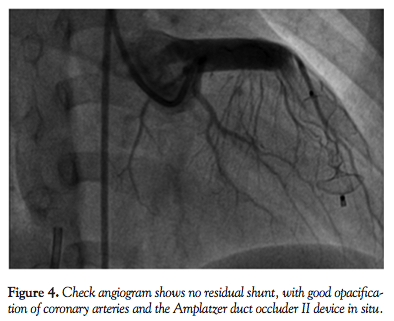

The guiding catheter was then withdrawn up to the right ventricular aspect of the fistula and the proximal retention skirt was released in the right ventricular end of the fistula (Figure 3). Repeat angiogram showed good position of the device with no residual shunt and better opacification of the coronary arteries (Figure 4). No complication occurred during or after the procedure. Electrocardiogram showed no changes. The patient was put on aspirin 5 mg/kg/day for 3 months. She was examined after 3 and 12 months and was asymptomatic with no murmur on clinical examination, and no residual shunt on echocardiogram.